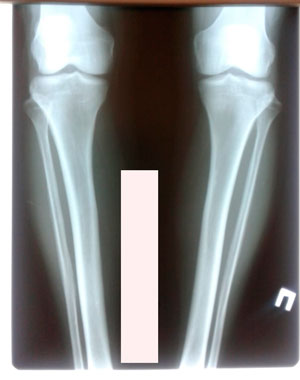

Рентген в 60 дней

Вложения